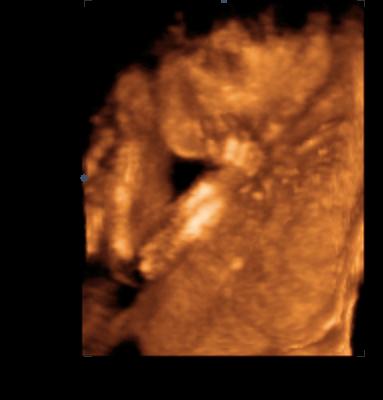

még az uhról ha nem gond

nagyon jófej volt adoktor bácsi végig beszélt,mutattta mi hol van,mindene szépen látszott,kivéve aneme és az arca,mivel a hátam felé befelé fordulva ALUDT ,persze egész nap még a rendelőbe is mozgott,aztán oldalra feküdtem akkor feléledt ,de csak addig amíg elnem kezdte az arcát fogdosni,újját próbálta szopizni akkor egyből elaludt megint.Persze úgyhogy lábak keresztbe,karok szorosan fej mellett,na szép

Amennyit látott belőle a doki azt mondta lány,de ez nem 100 %.

40 deka felett van egy kicsit a picúr

egyenlőr ezeket a képeket tudom megmutatni és csináltam pocisat is

igen úgy tűnik rendben minden,minden alkatrész a helyén van